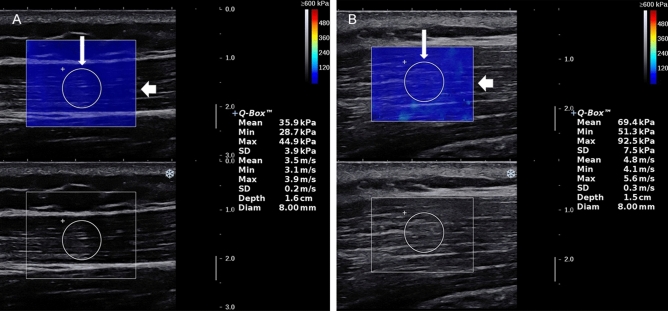

The device used to obtain B-mode and SWE images of the UT was Aixplorer US system (SuperSonic Imagine, Aix-en-Provence, France), with an SL 15–4 linear probe operating at 4–15 MHz. US device parameters were as follows: the superficial musculoskeletal preset in the standard default mode, smoothing level 5, persistence high and 0–600 kPa (scale). The tip of transducer covered with several millimeters of ultrasound gel was placed smoothly to the targeted area of UT along perpendicular direction to the skin22,23. It was of importance to ensure that there was no pressure between skin and the probe. The operator maintained the transducer for a few seconds to obtain a stable SWE image. The size of the square region of interest (ROI) was adjusted according to UT thickness. ROI depth varied between 0.5 cm and 2.5 cm from the skin because the targeted UT muscle fibers are consistently parallel, superficial, and ROI colormap was stable and even in this study. Mean SWV was measured in a round area called Q-box: the size of Q-box was fixed as a diameter of 8 mm, Q-box positioning was at the center of the ROI, avoiding the deep and superficial fascia of the UT. Shoulder abduction positions for bilateral examination of each participant were as follows: (i) shoulder 0° abduction (L0° and R0°), (ii) shoulder 90° passive abduction (L90° and R90°). To avoid the influence of scapular depression and shoulder joint rotation on the UT elasticity24, all the participants were strictly examined according to the following specific procedure: (i) During shoulder 0° abduction, the participants sat and stayed fully relax, and upper arm rested gently against the chest wall (0° abduction angle), with upper arm in the same plane of the chest wall, forearm in pronation, forearm and hand resting flat on top of hip and thigh; (ii) During shoulder 90° passive abduction, arm was passively positioned at shoulder 90° abduction on a plinth supported with the arm in the same plane of the chest wall, with the elbow fully extended and the thumb pointed to the ceiling (performed in the frontal plane at 90° abduction angle). The angle of shoulder abduction was measured by a manual goniometer to ensure the reliability and consistency. Figure 1 illustrates that the system automatically calculated the SWV values for the Q-box area expressed in m/s at R0° and R90°.

Figure 1.

SWE-mode (top panel) and B-mode (bottom panel) ultrasound images of the UT. A color map of UT elasticity is shown in the square region of interest (ROI) (thick arrow). The mean SWV in the round Q-box (thin arrow) is presented on the right side of the image. A,B show that the size of the Q-box is 8 mm in diameter. The mean SWV of a healthy volunteer at R0° was 3.5 m/s (A), the mean SWV at R90° was 4.8 m/s (B).